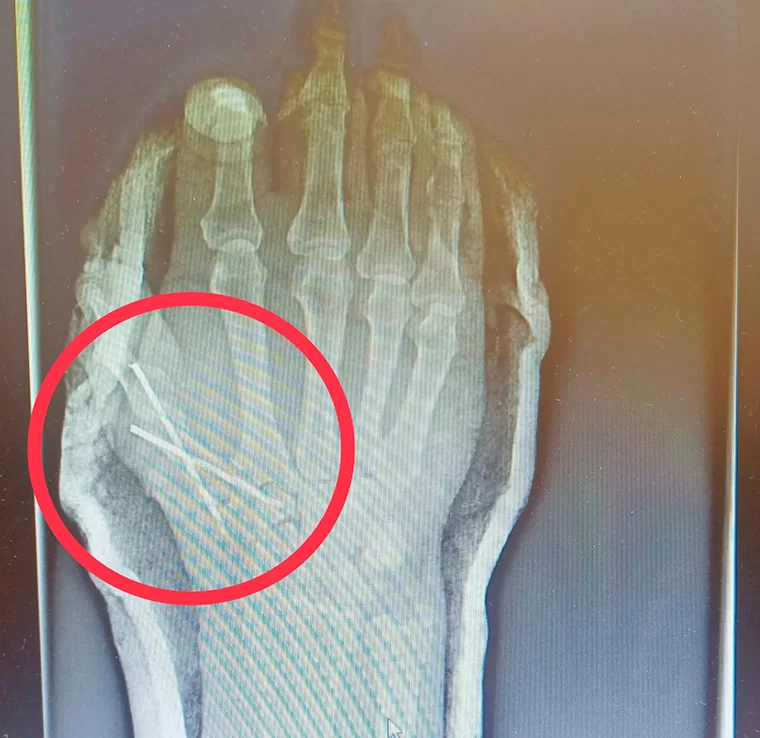

В больнице установили, что мужчина порезал себе руку, повредив сухожилия, и получил перелом основания пястной кости со смещением. В экстренном порядке его прооперировал врач травматолог-ортопед Марат Шахбанов. Ему помогала операционная медицинская сестра Энже Газизова.